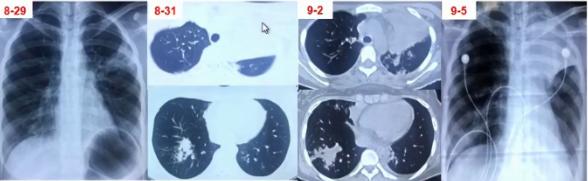

图6 患者在院外胸部影像学变化。左上肺小块实变,逐渐累积至右下肺,而且左上肺实变扩大和膨胀不全。

病例6

女性,14岁,学生。发热、咳嗽10天入院。

院外治疗经过

• 第1-3天:阿奇霉素治疗3天(口服2天+静脉1天)无效,胸片示左上肺及右下肺斑片影

• 第4-5天:头孢曲松+阿奇霉素+小剂量激素2天无效,肺CT示左上肺大片实变及右下肺斑片影

• 第6-7天:头孢曲松+阿奇霉素+甲泼尼龙40mg bid 2天仍无好转,出现呼吸困难,CT示肺内病变进一步增多,血常规7.8×109/L、N 82.9%,CRP 43.16 mg/L,动脉血气分析PH7.42 PaO246mg Hg。

• 第8-9天:美罗培南+利奈唑胺+甲泼尼龙 80mg/d,体温无下降,呼吸困难加重,吸氧8-10L/min,指脉氧80%左右,G试验154.7,加用伏立康唑,行气管插管机械通气,病情仍无改善转来我院。

院外病原学检查结果

• 痰涂片:偶见G+球菌 呈双排列

• 痰培养:少量假丝酵母菌

• CMV IgG 0.8AU/ml(<6),IgM 0.32(<0.85)

• 甲流及乙流抗原阴性

• 呼吸道病原九项IgM(包括嗜肺军团菌、肺炎支原体、肺炎衣原体等)均阴性

图7 患者入院当日病情小结

图8 患者入院当日胸部CT。左上肺大面积实变,右上肺斑片影,出现胸腔积液

病原学诊断

入院第1日:痰培养无菌生长;痰涂片:少量G-球菌,未见真菌;血培养:5天无菌生长(普通+厌氧);GM抗原:小于0.25μg/L;G试验:96.5pg/ml

入院第2日:BALF-mNGS:肺炎支原体;BAL涂片:未找到细菌真菌、未找到抗酸菌

入院第9日肺炎支原体抗体:>1:1280

治疗转归及误诊原因分析

①转归

美罗培南+米诺环素治疗48小时后退热;住院治疗第5天撤机拔管;住院治疗第10天停用美罗培南;米诺环素疗程共30天;住院34天出院。

②初始治疗失败原因分析

• 临床和影像表现不典型:实变、呼衰、高凝

• CAP常规初始经验性治疗无效:肺炎支原体大环内酯类抗生素耐药

• 缺乏肺炎支原体感染的早期诊断技术